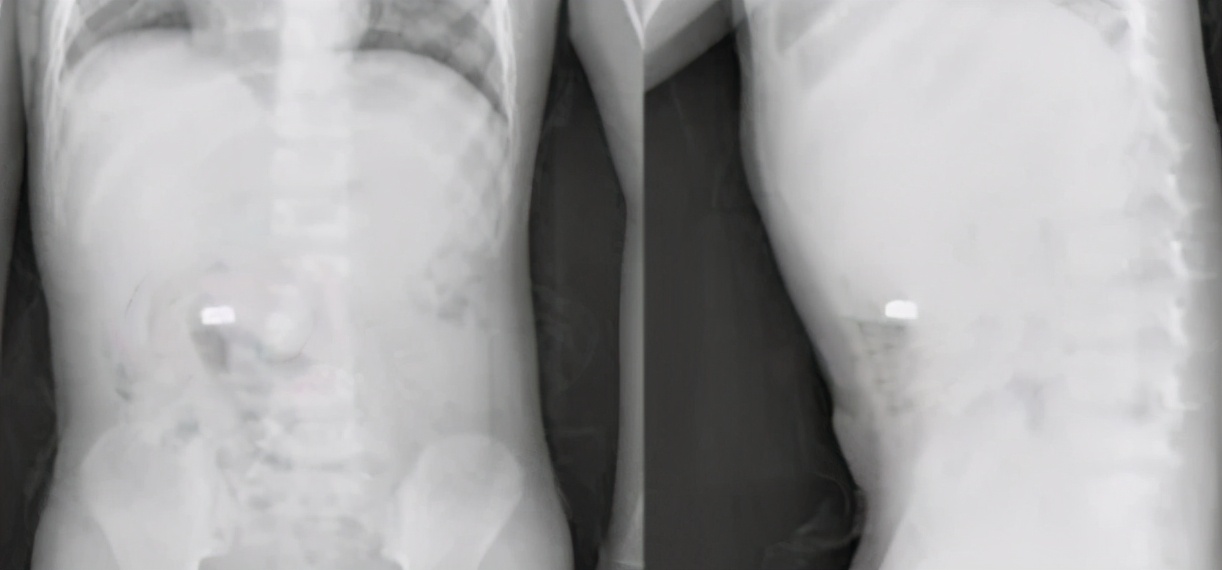

话音刚落小刘就带着儿子去医院进行检查,通过半天的检查,拍片显示孩子的食道并没有堵住,要是卡在孩子的食道内将会带来致命的危险,等到家人来看望孩子之后,爷爷也表现的十分的自责。